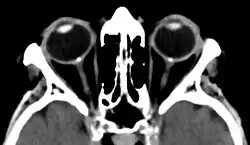

Bilateral optic disc drusen in computed tomography seen as dense spots at the optical disc